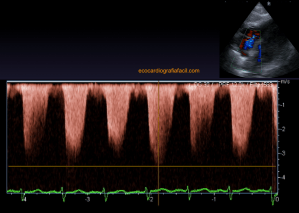

141. Mediciones de los planos paraesternales.